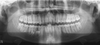

Horizontal bone loss with intact apex – diagnosis?

A

• Periodontitis chronica

• (chronic periodontitis).

• Treatment: Periodontal therapy

Severe generalised bone loss with marked mobility – diagnosis?

• Periodontitis chronica gravis

• (advanced chronic periodontitis).

• Treatment: Extraction

* Periodontitis chronica * (Chronic periodontitis) → Horizontal bone loss, apex normal

* Periodontitis chronica gravis * (Advanced chronic periodontitis) → Severe bone loss ± furcation involvement